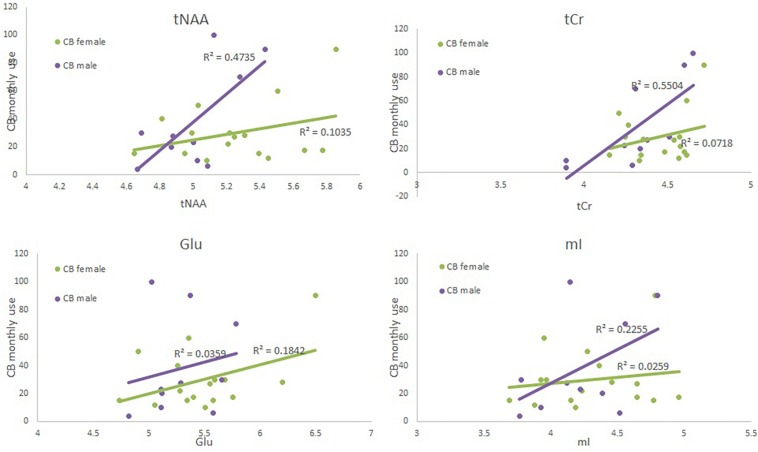

The ANOVA failed to show an effect of group or sex (F < 1); additionally the interaction was also not significant [F(1,49) = 1.87, p = 0.18]. Both regression models were significant (see Table 4 and Figure 2). CB monthly use significantly predicted tCr levels in both the model with and without the interaction term. Sex was marginally significant in the model without the interaction term but significant in the model with the term.

Glu

The ANOVA failed to show an effect of group or sex (F < 1); additionally the interaction was also not significant [F(1,49) = 2.53, p = 0.12]. Both regression failed to reach significance (see Table 5 and Figure 2). When examining each predictor variable the parameter estimate for monthly use appears to be modulated by the introduction of the interaction term to the model (although the factor is not significant when corrected for multiple comparisons) suggesting that the effect of monthly CB use is different for males and females. However, these results should be interpreted with great caution given the small sample size and small effect size.

The ANOVA failed to show an effect of group or an interaction between group and sex (F < 1). However, there was a significant effect of sex [F(1,49) = 7.44, p = 0.009]; females had a higher level of tNAA than did males. Neither regression model was significant (see Supplementary Table S5, Supplementary Figure S1, and Figure 2). When examining the predictor variables sex approached significance.

mI

The ANOVA failed to show an effect of group or sex (F < 1); additionally the interaction was also not significant [F(1,49) = 2.7, p = 0.11]. Neither regression model was significant (see Supplementary Tables S1, S4, Supplementary Figure S1, and Figure 2).